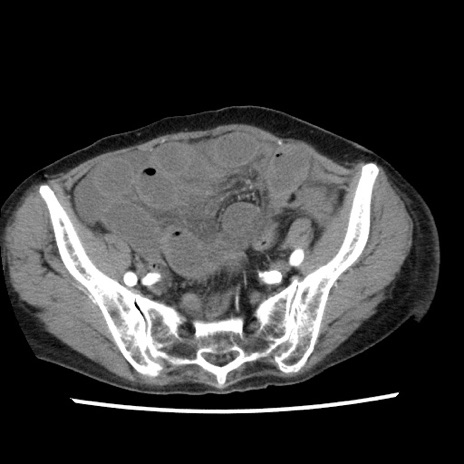

症例1(横断像)

【症例】80歳代女性

【主訴】腹痛

【現病歴】8時間前から腹痛あり来院。

【既往歴】糖尿病、脂質異常症、子宮体癌にて子宮全摘術

【身体所見】意識清明・会話良好だが腹痛で苦悶様、全腹部にわたって反跳痛と圧痛あり

【データ】WBC 13600、CRP 0.14、LDH 224、CK 90